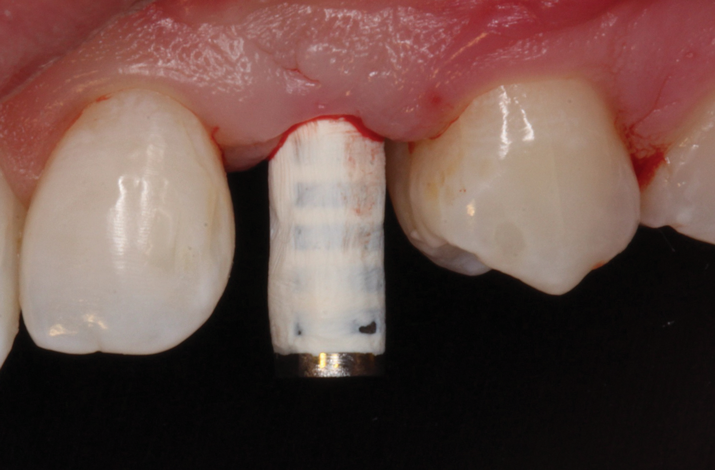

(40.) Following removal of the partially completed provisional restoration from the mouth, the emergence area is filled in with flowable composite and refined to create a narrow S-curve emergence profile.

Figure 40

(41.) Following removal of the partially completed provisional restoration from the mouth, the emergence area is filled in with flowable composite and refined to create a narrow S-curve emergence profile.

Figure 41

(42.) The remaining portion of the titanium abutment was cut off, and the palatal aspect was undercontoured.

Figure 42

(43.) The remaining portion of the titanium abutment was cut off, and the palatal aspect was undercontoured.

Figure 43